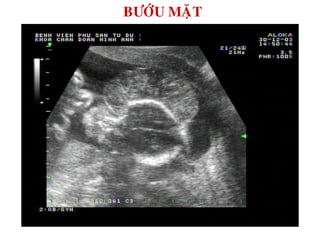

BÖÔÙU MAËT